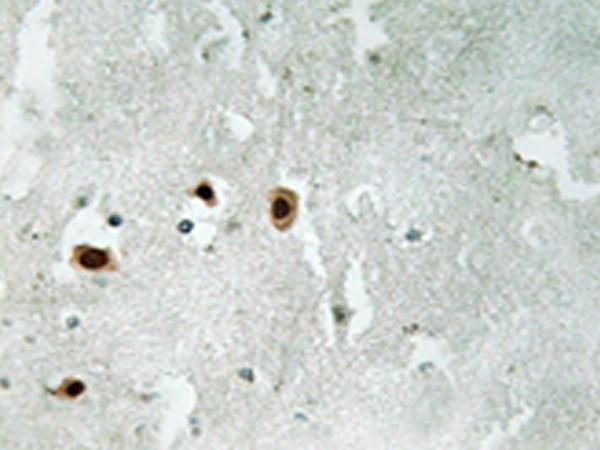

IHC |

IHC positive control: |

Human brain tissue |

IHC Recommend dilution: |

50-100 |